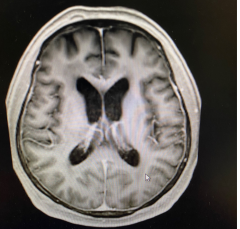

已经步入中年的刘先生,饱受颅内淋巴瘤晚期的折磨。今年三月份,全国正处在新冠疫情攻坚战时期,许多医院放射治疗科采取了闭诊举措。就在那个社会恐慌、正常医疗资源紧张的关口,刘先生一家来到了在疫情期仍然坚持接诊的清华大学附属北京清华长庚医院放射治疗科就诊。科主任黎功对接诊的场景至今记忆犹新,躺在担架床上的患者已出现意识模糊,自主行动能力丧失,大小便失禁等症状,情况不乐观。经评估,黎功为患者采取了“放疗+免疫”的治疗疗法,即进行放射治疗的同时,采用最新的免疫药物联合治疗。经过几个疗程治疗后,刘先生不仅恢复了自主行动能力,经影像学检查,患者颅内的淋巴瘤也已消失,达到了康复的标准。

治疗前(红色区域为肿瘤)                治疗后5个月肿瘤消失